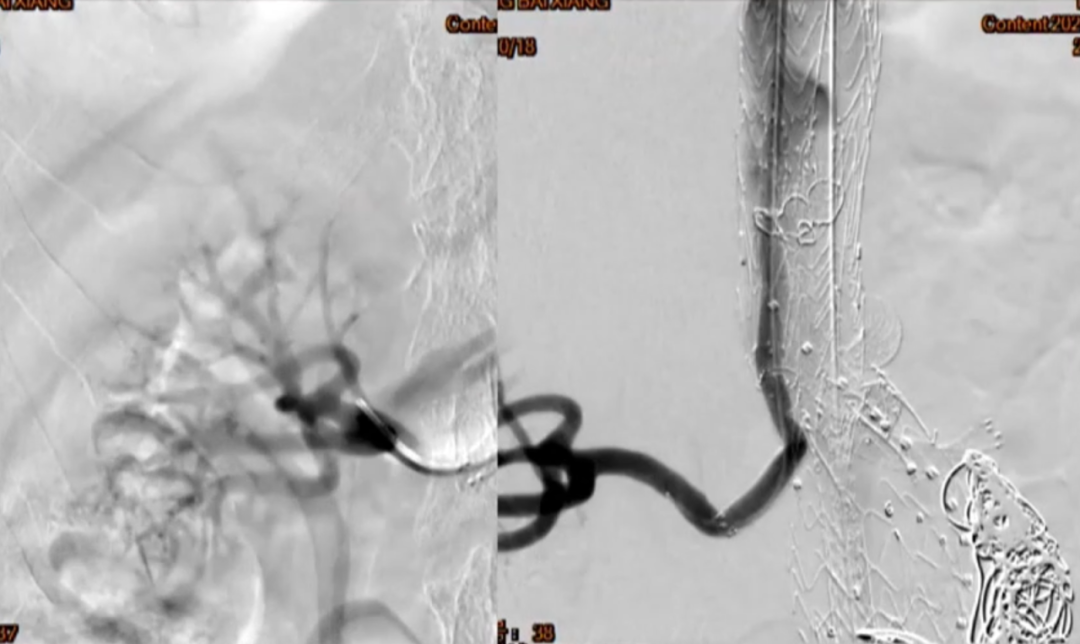

超选SMA,桥接8-100mm Viabahn,内衬8-60mm Absolute裸支架

超选CA,桥接8-100mm Viabahn

超选RRA烟囱支架,桥接6-100mm+6-50mm Viabahn

超选LRA烟囱支架,桥接6-100mm Viabahn

术后造影